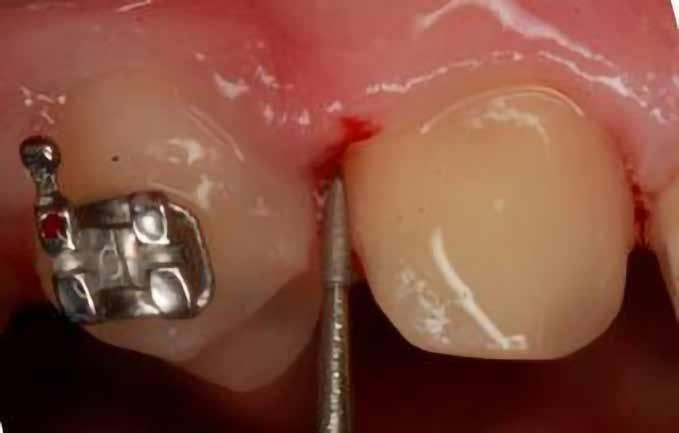

sok korrigálása, valamint az impaktálódott fog előtöréséhez szükséges hely megteremtését követően, egy merev acél ív segítségével stabilizáltuk a fogakat. Ezt követően elvégeztük a jobb felső nagymetszőfog sebészi feltárását. A fog koronáját csupán lágyrész borította, ezért nem volt szükség a csontállomány elvételére. A felszabadítás során egy 975

nm-es hullámhosszon pulzáló üzemmódban alkalmazott lézert használtunk (LaserHF standard, Hager & Werken). A teljesítménye 3 W, az aktív ciklus-idő 50%-os, a vezetőszál átmérője pedig 0,4 mm volt (2. ábra). A lézert 150 másodpercen keresztül alkalmaztuk. A fogat borító lágyrészek eltávolítását követően egy láncos brekettet rögzítettünk a metszőfog bukkális felszínére. A műtétet követően nem tapasztaltunk vérzést, nem alakult ki oedema, valamint a páciens sem számolt be fájdalom vagy bármely egyéb kellemetlenség fennállásáról. A felszabadítást követően a páciens minden hónapban háromszor jelent meg a felszabadított területre ránövő lágyrészek és az íny lézeres eltávolítása céljából. A beavatkozások során ugyanazt a lézer készüléket használtuk, mint amivel a felszabadítást végeztük. Közvetlenül a felszabadítást követően megkezdtük a fog finom extrudálását a láncos breketthez kötött füzérgumi segítségével.

30 e-Journal ORTHODONTIA

2. ábra: Az impaktált fog lézerrel asszisztált sebészi feltárása. 3. ábra: A kezelés megkezdését követő 15. hónapban megfigyelhető a sikeres felszabadítást, fogmozgatást és pozicionálást követően látható állapot.

A 975 nm-es hullámhosszt elsősorban sebészi beavatkozások végzése során alkalmazzák. Az ezzel a hullámhosszúsággal rendelkező lézersugarak csak kis mélységben képesek a lágyrészeket penetrálni, valamint hagyományosan nem ezeket szokták biostimuláció során használni. Ugyanakkor minden sebészi célra alkalmazott lézer körül megfigyelhetünk egy csökkenő intenzitással (azaz fényerővel) rendelkező gyűrűt, amely perifériáján biostimulációs hatások is létrejöhetnek. Az alacsony energiájú lézeres terápia (low-level laser therapy; LLLT) során a lézeres fejet a lágyszövetektől nagyobb

távolságban vezetve, az alábbi paraméterek mellett alkalmaztuk: pulzus üzemmód, 100 mW teljesítmény, 660 nm-es hullámhossz. A lézeres fejen lévő nyílás nagysága 0,125 mm2 volt (0,4 mm átmérő). A biostimuláció során egy megközelítőleg 7 cm2-es területet világítottunk meg a kérdéses fog vesztibuláris és palatinális oldalának megfelelően. A megvilágítás időtartama minden találkozó során 150 másodperc volt. A leadott energia 15 J, az energiasűrűség pedig 17J/ cm2 körül mozgott. A lézeres terápiát a kívánt fogpozíció eléréséig minden hónapban megismételtük. Ez a folyamat

6 hónapon keresztül tartott. Ennek megfelelően a fog körül található szövetek a felszabadítás, valamint a havi kontrollok során 975 nm-es (több mint 25 J/cm2 energiasűrűség) és 660 nm-es hullámhosszúságú (12–18 J/cm2 energiasűrűség) lézersugarakkal is megvilágításra kerültek. Az impaktálódott fogat megközelítőleg 7 hónap alatt tudtuk megfelelő pozícióba mozgatni (3. ábra). Az orthodoncia kezelés aktív szakasza 18 hónapon keresztül tartott. A fogívek végső nivellálását és a fogak végleges pozícióba rendezését 0.018 × 0.025-ös acélívekkel végeztük.

A kezelés befejezésekor a páciens mosolya drámai mértékben javult, továbbá a frontfogak elhelyezkedése és az ínyszél lefutása is szemmel látható módon kedvezőbbé vált (4. ábra). A kezelés végén készült CBCT felvétel nem mutatta

csontfelszívódás jelenlétét, és csupán minimális mértékű gyökérfelszívódás bekövetkezését igazolta.

Összefoglalás

A lágyrészekkel fedett fogak sebészi felszabadítása során alkalmazott lézerek, továbbá a fogmozgatás gyorsítására alkalmazott alacsony energiájú lézeres terápia kombinálása kedvező hatással lehet az impaktált fogak kezelése céljából alkalmazott terápia kimenetelére. Ez különös mértékben igaz lehet a dilacerált gyökerekkel rendelkező fogak esetében. Ez a megközelítés jelentősen javíthat az eset várható prognózisán. A kiegészítő kezelés révén a parodontális szö-

A lézerrel asszisztált felszabadítás előtt készített felvétel.

A végső állapotról készült periapikális felvétel.

készült felvétel.

vetek egészsége, az okkluzális viszonyok minősége, valamint az esztétikai megjelenés is kedvezőbb lehet. Ez a hatás még látványosabb lehet fiatal páciensek esetében.